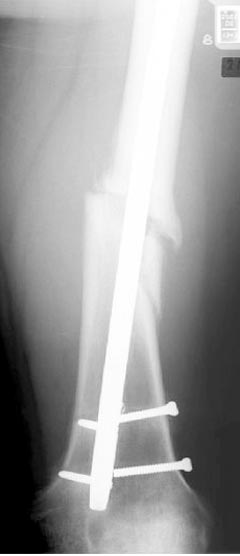

Лечение бедра - ургентное оперативное лечение антеградным с минимально рассверливанием, фиксацией с минимальным диаметром штифта и плюс irrigation and debridment и с закрытием поперечной до 10 см раны на уровне перелома в день поступления.

Снимки представлены: 1 мес; 3 мес; 1 год; 2 года, предоперационные и ротационная КТ грамма

Деформация:

Вальгус- 17 градусов

Рекурватум 5 градусов

Укорочение 2.5см

Ротационно 22 градусов внутренная

Смещение диафиза по поперечнику 75%

Операцию провели в два этапа, сперва удалили штифт, рассверливание римером на пару мм большего диаметра, определение чувствительности на анаэробную и аэробную культуру (где исследования показали негативный результат чувствительности), через дней десять - начали аппаратную фиксацию.